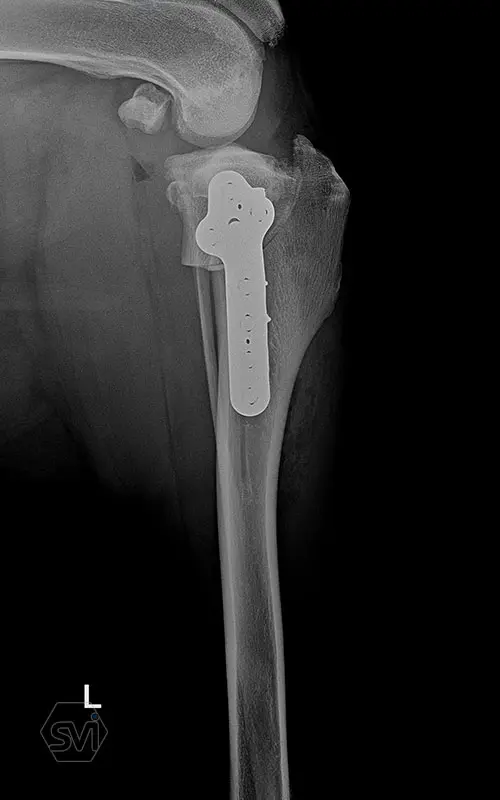

The precontoured polyaxial locking TPLO family has become complete in the smartvetimplants.com offer

Introducing the precontured polyaxial locking TPLO family, now available in all sizes:

- Mini: 2.0mm (thinner and thicker version)

- Midi: 2.4mm

- Small: 2.7mm

- Standard: 3.5mm (both in short and extended versions)

- Giant: designed for 4.0mm screws.

It has a number of advantageous features that make it stand out from standard TPLO solutions:

- well designed that follows the anatomical position and ideal hole placement

- precontoured, its use shortens the surgical time, no greater physical force is required for bending

- locking system for greater stability

- polyaxial screw insertion, the direction of screw insertion can be freely selected in a 30-degree circle while maintaining angular stability! (this is very useful to avoid driving the screw into the joint, and the temporary fixing can also be avoided with a K-wire)

- outstanding quality product, made in EU, in Hungary, and holds its own on both the European and American markets.